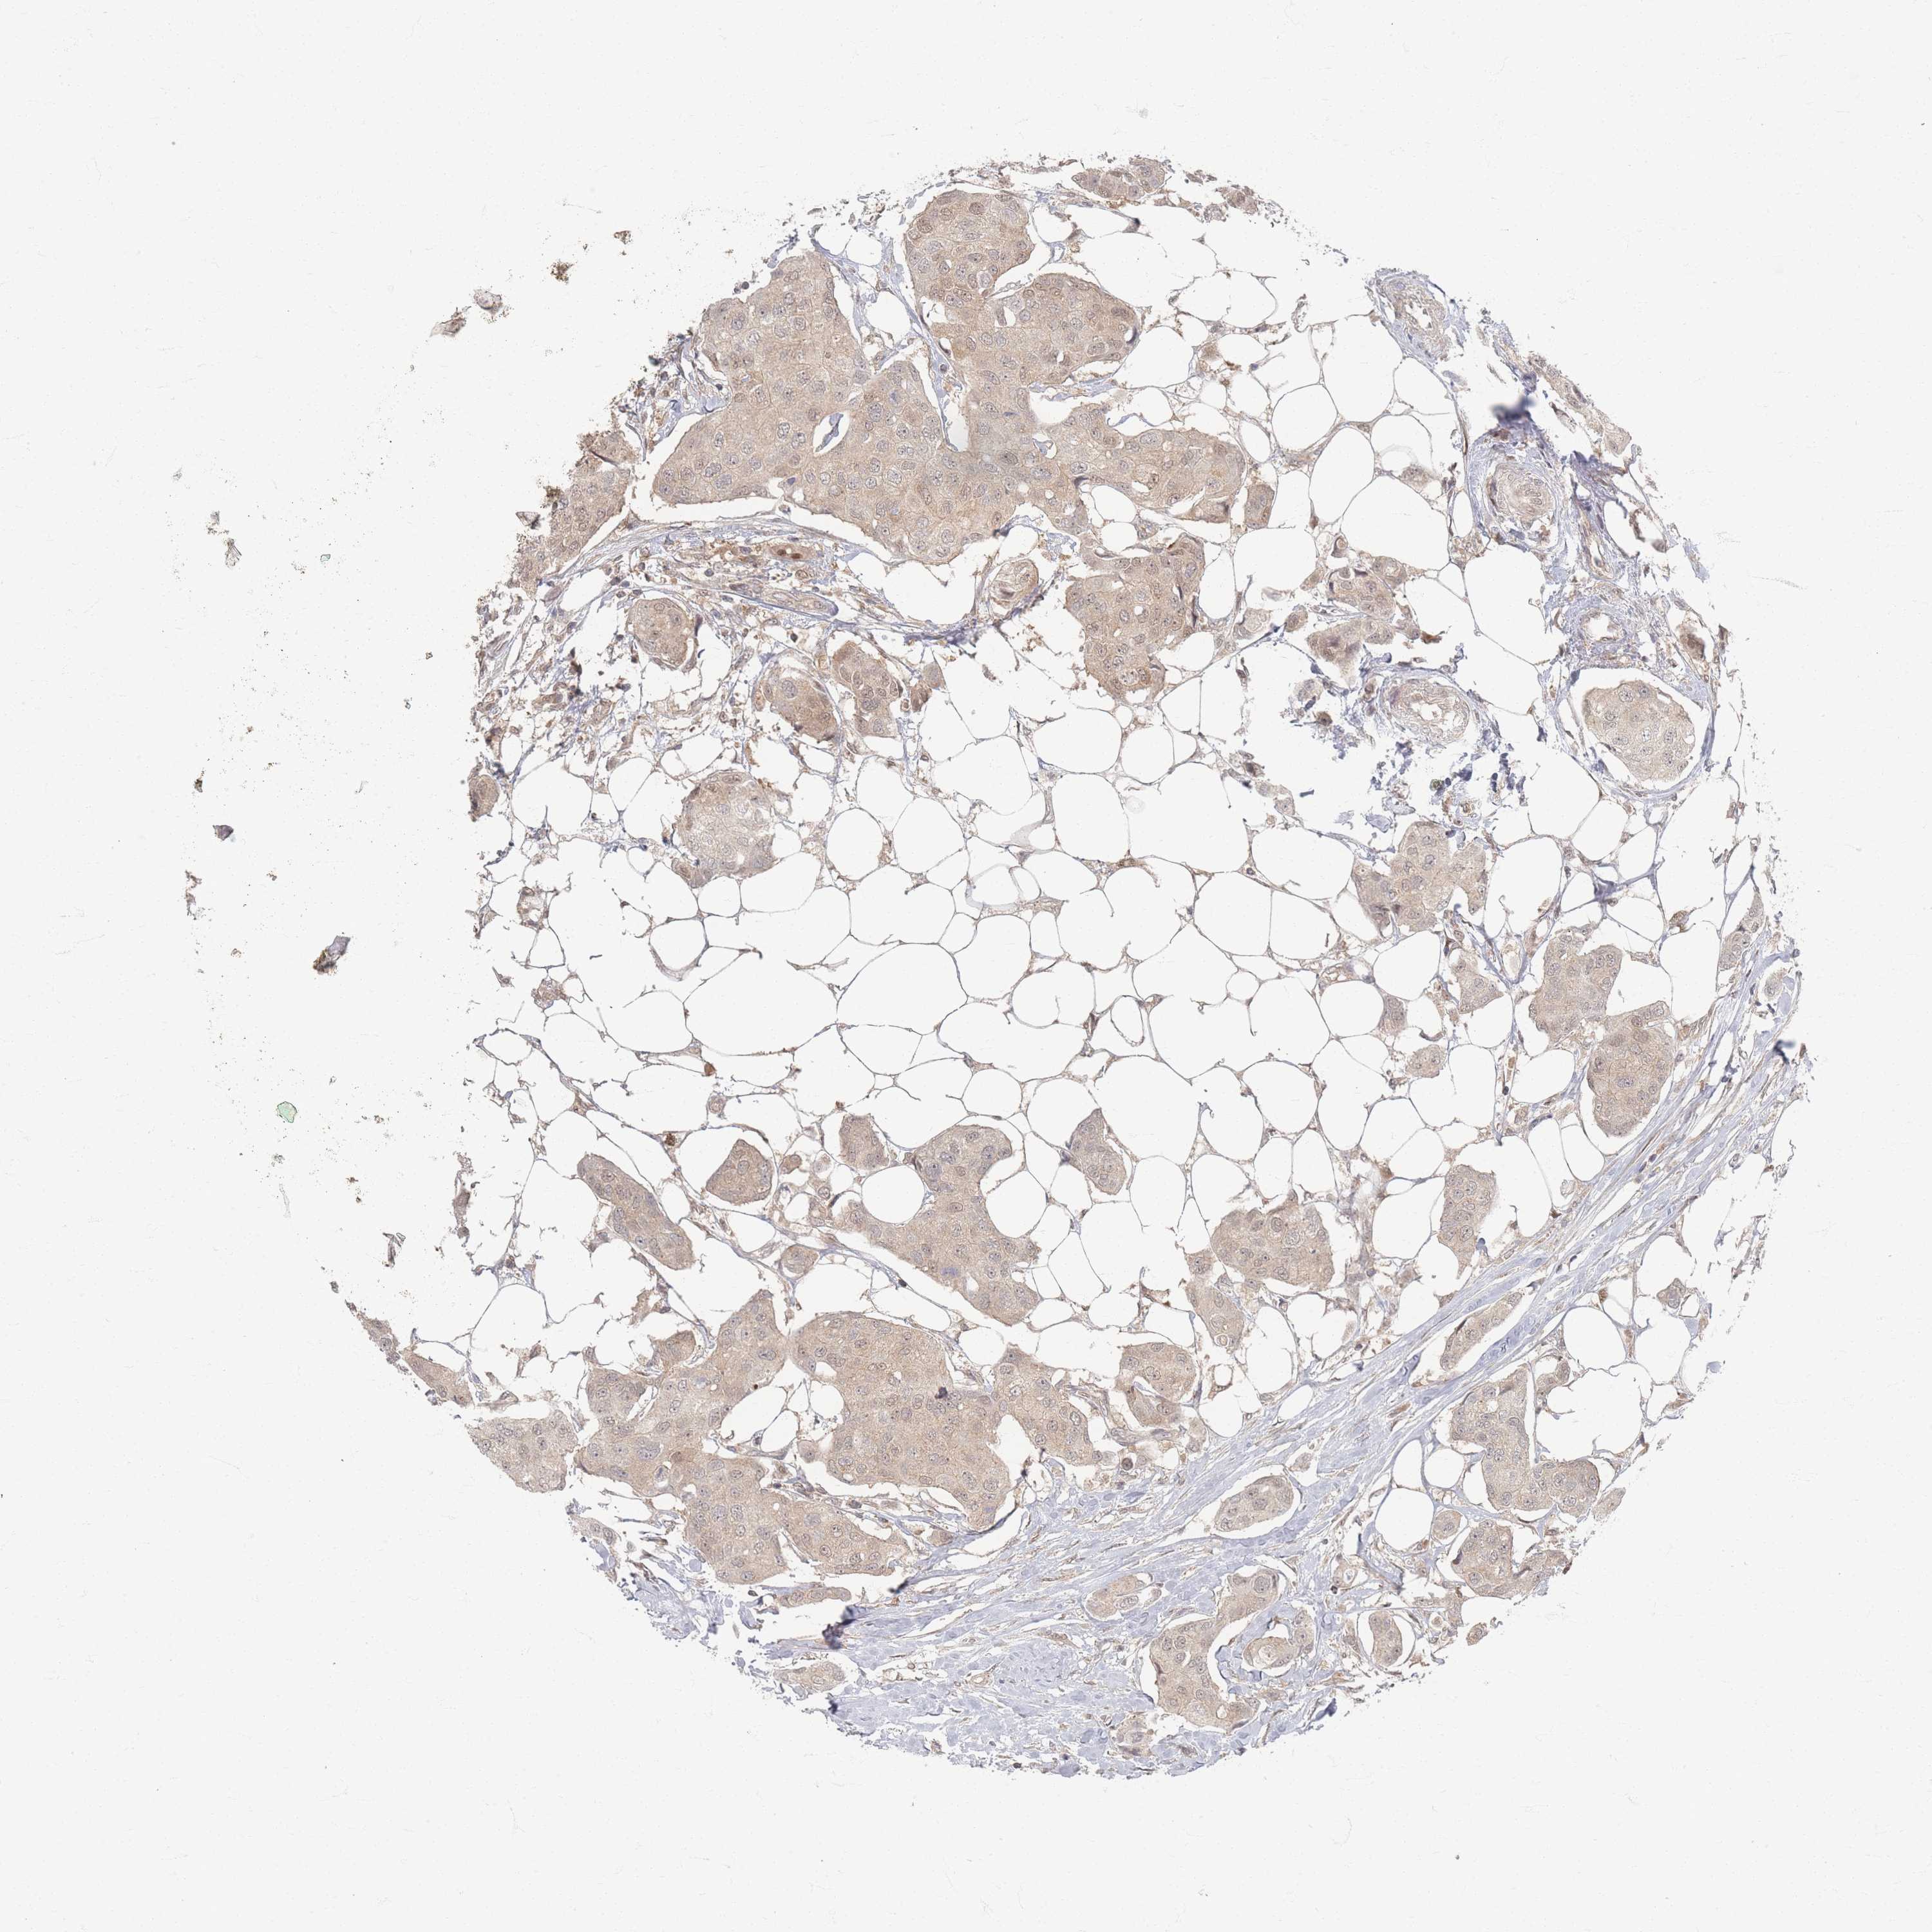

CANCER BREAST CANCER Show tissue menu

BRCA TCGA BRCA VALIDATION PROTEIN EXPRESSION